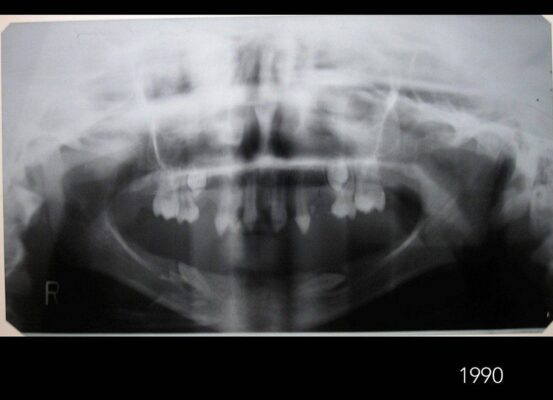

¿Qué es la Displasia Ectodérmica?

Displasia ectodérmica: una enfermedad presente y poco conocida.¿Qué es? ¿A quiénes afecta? ¿Cómo se produce? La displasia ectodérmica es un conjunto de enfermedades genéticas que afectan al ectodermo;